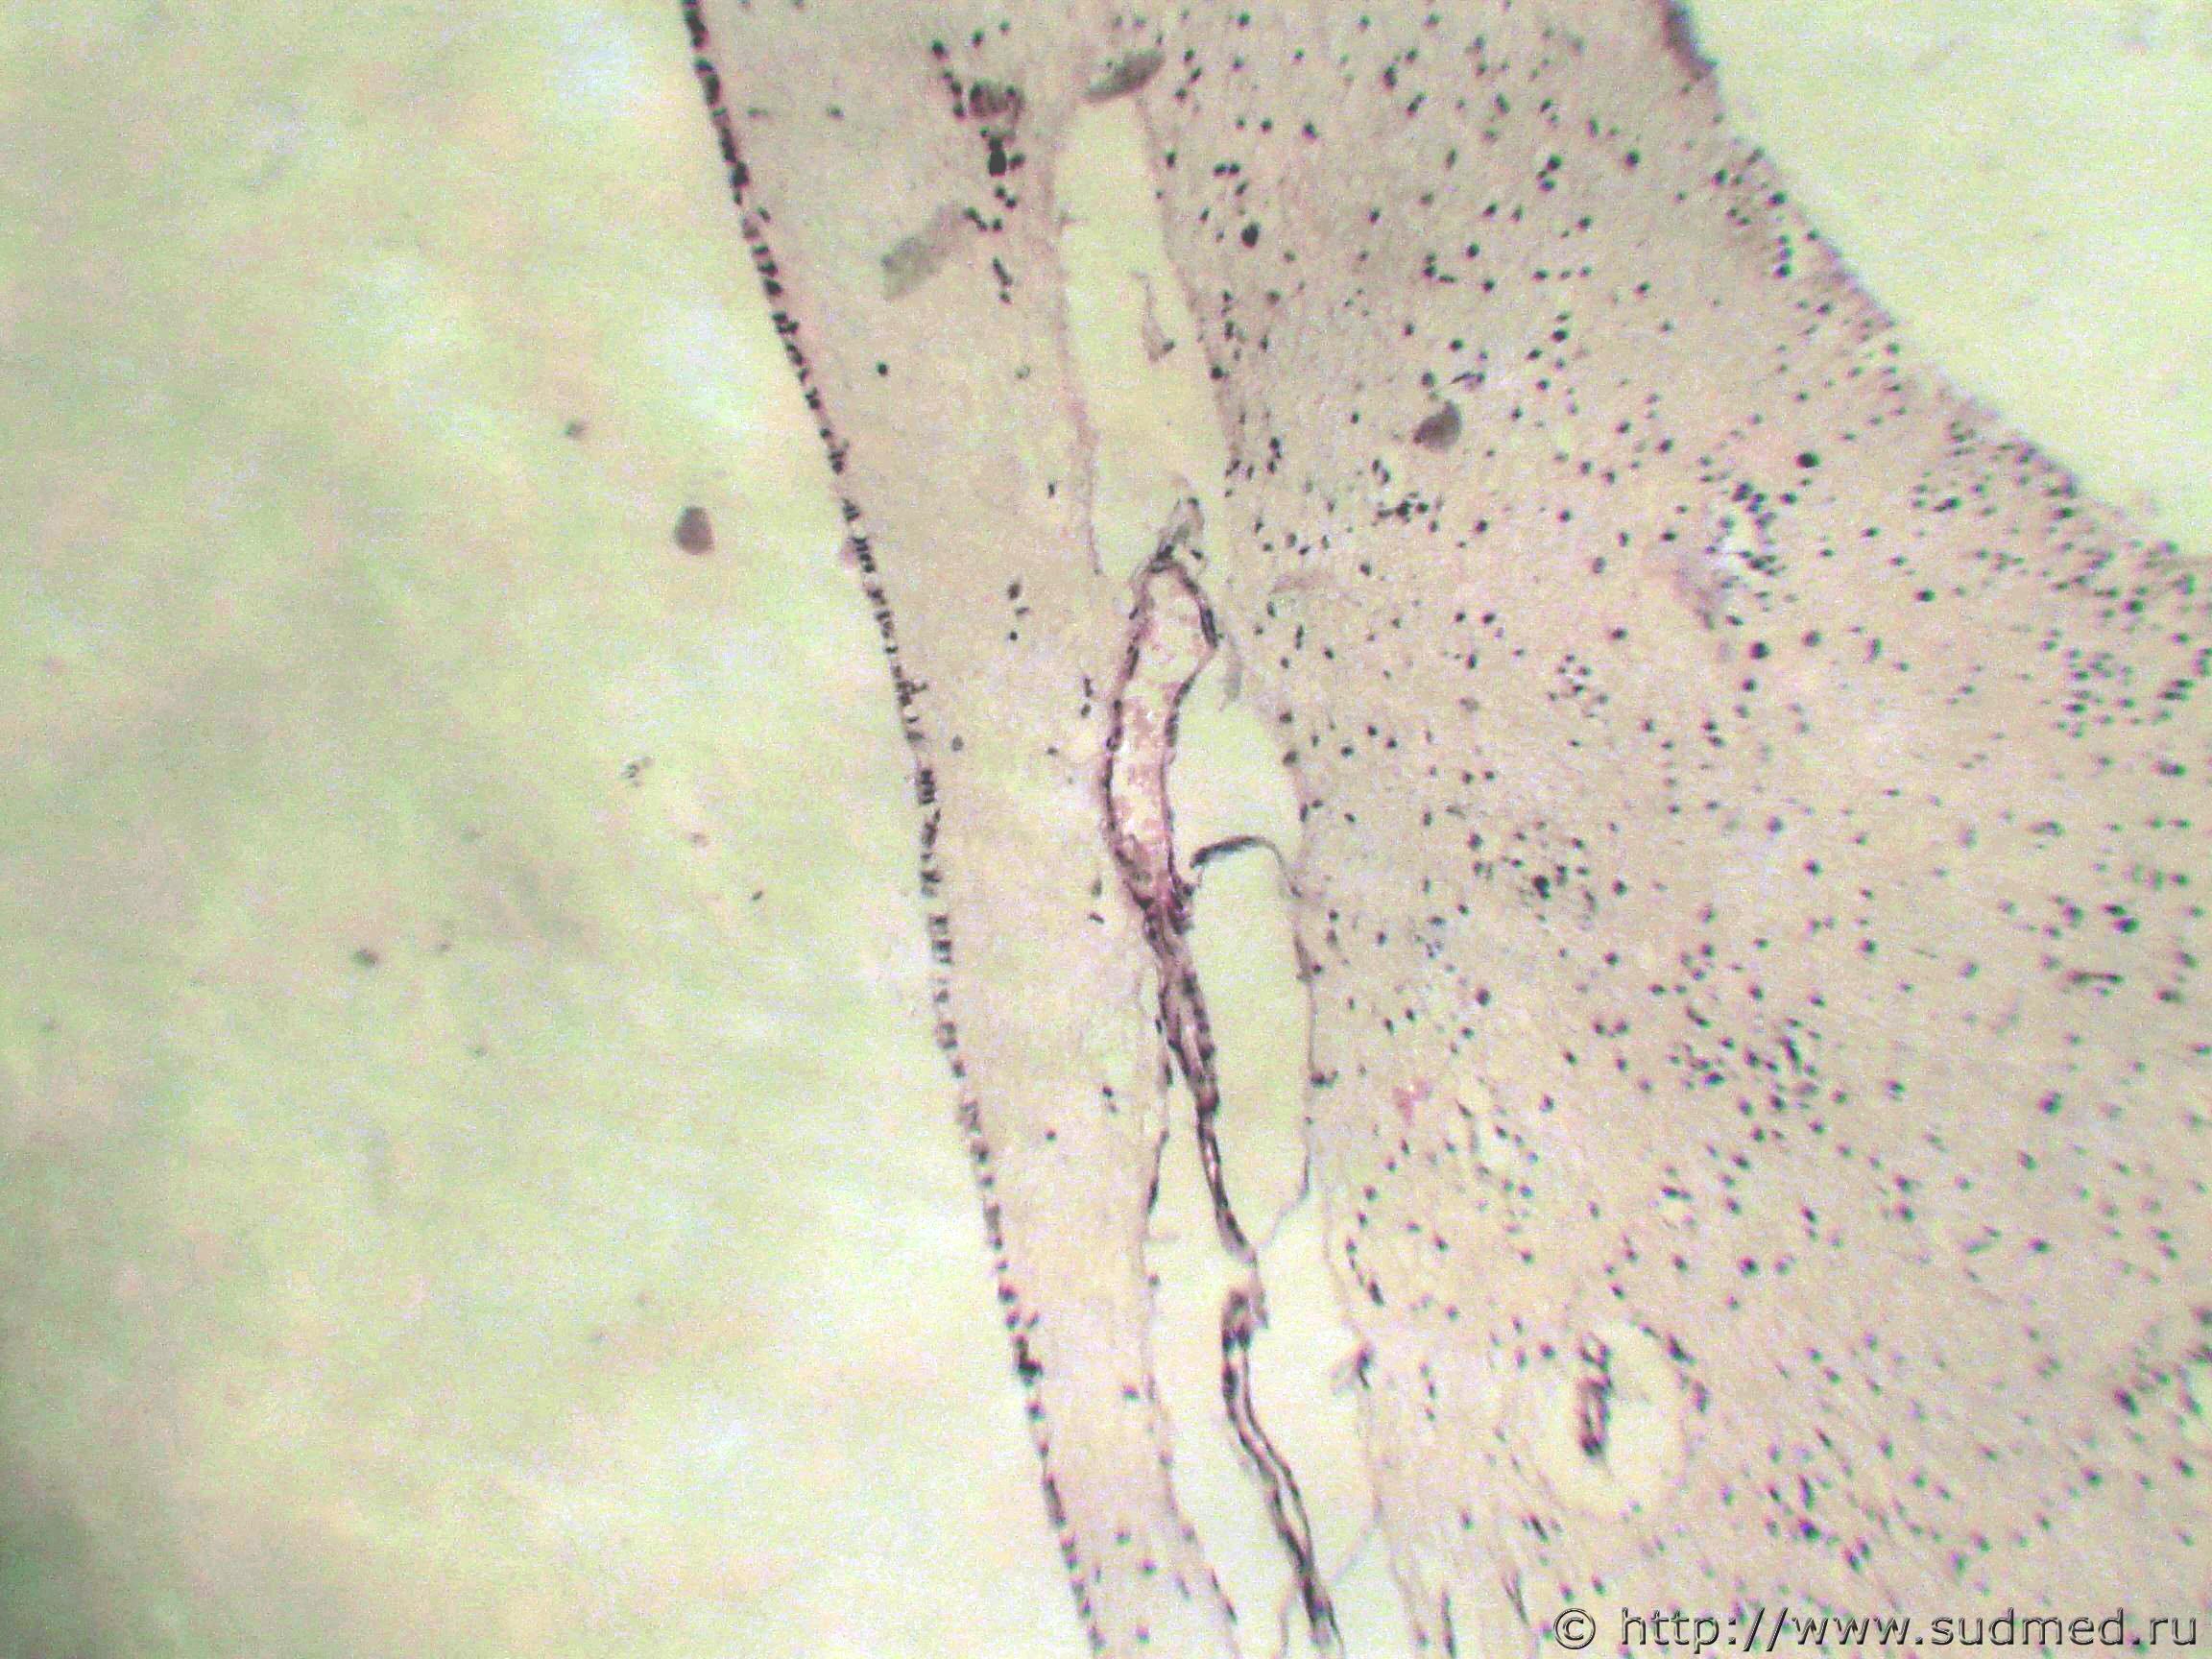

Гематоксилиновые шары.